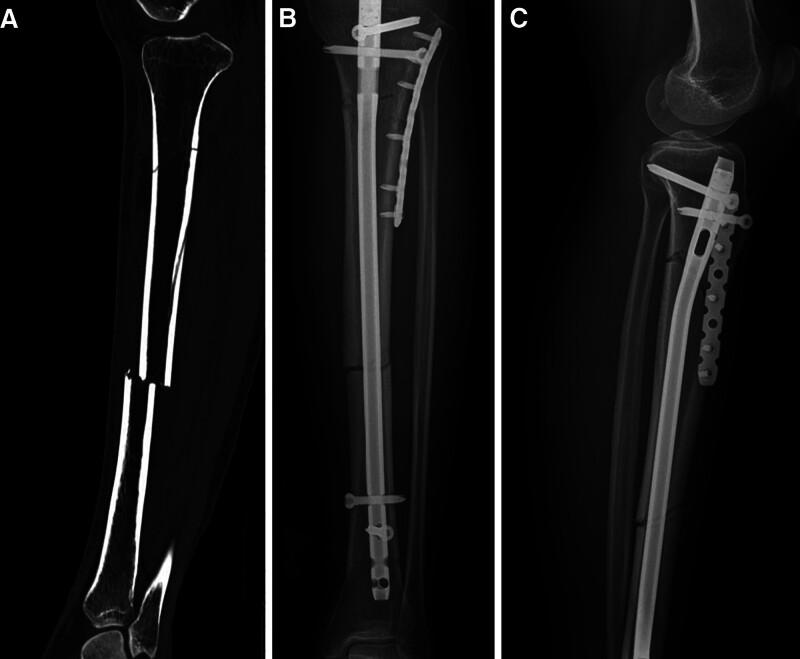

It is unclear whether small plates are needed for augment fixation to provide a more stable mechanical environment in segmental fractures of the tibia treated with intramedullary nail. The purpose of this study was to investigate the efficacy of intramedullary nailing combined with locking plates in the treatment of segmental fractures of the tibia. This study included 41 patients with segmental tibia fractures between January 1, 2018 and January 1, 2023. Eighteen patients were treated with an intramedullary nail assisted by a locking plate (combination group), and 23 patients were treated with an intramedullary nail without a plate (nail group). The perioperative parameters of all patients were recorded, and clinical efficacy was evaluated during follow-up. The operation time was shorter but the incision was longer in the combination group (P < .05). The numbers of fluoroscopy procedures and the time to union were shorter in the combination group (P < .05). The rate of malunion in the nail group (4, 17.4%) was significantly greater than that in the combination group (0, 0%). At the last follow-up, no statistically significant differences in walking ability were detected. Our results suggest that a locking plate combined with an intramedullary nail for segmental tibial fractures may require a longer surgical incision, but it has significant advantages such as a shorter operative time and time to union, a shorter fluoroscopy time, and a lower rate of malunion and nonunion. Intramedullary nail fixation assisted by a locking plate is an effective method for treating segmental fractures of the tibia.

对于在使用髓内钉治疗的胫骨节段性骨折中,是否需要小钢板进行增强固定以提供更稳定的力学环境尚不清楚。本研究的目的是探讨髓内钉联合锁定钢板治疗胫骨节段性骨折的疗效。本研究纳入了2018年1月1日至2023年1月1日期间的41例胫骨节段性骨折患者。18例患者采用锁定钢板辅助髓内钉治疗(联合组),23例患者采用无钢板髓内钉治疗(髓内钉组)。记录所有患者的围手术期参数,并在随访期间评估临床疗效。联合组手术时间较短但切口较长(P < 0.05)。联合组的透视次数和骨折愈合时间较短(P < 0.05)。髓内钉组的畸形愈合率(4例,17.4%)显著高于联合组(0例,0%)。在最后一次随访时,未检测到步行能力的统计学显著差异。我们的结果表明,锁定钢板联合髓内钉治疗胫骨节段性骨折可能需要更长的手术切口,但具有手术时间和骨折愈合时间短、透视时间短以及畸形愈合和不愈合率低等显著优势。锁定钢板辅助髓内钉固定是治疗胫骨节段性骨折的有效方法。